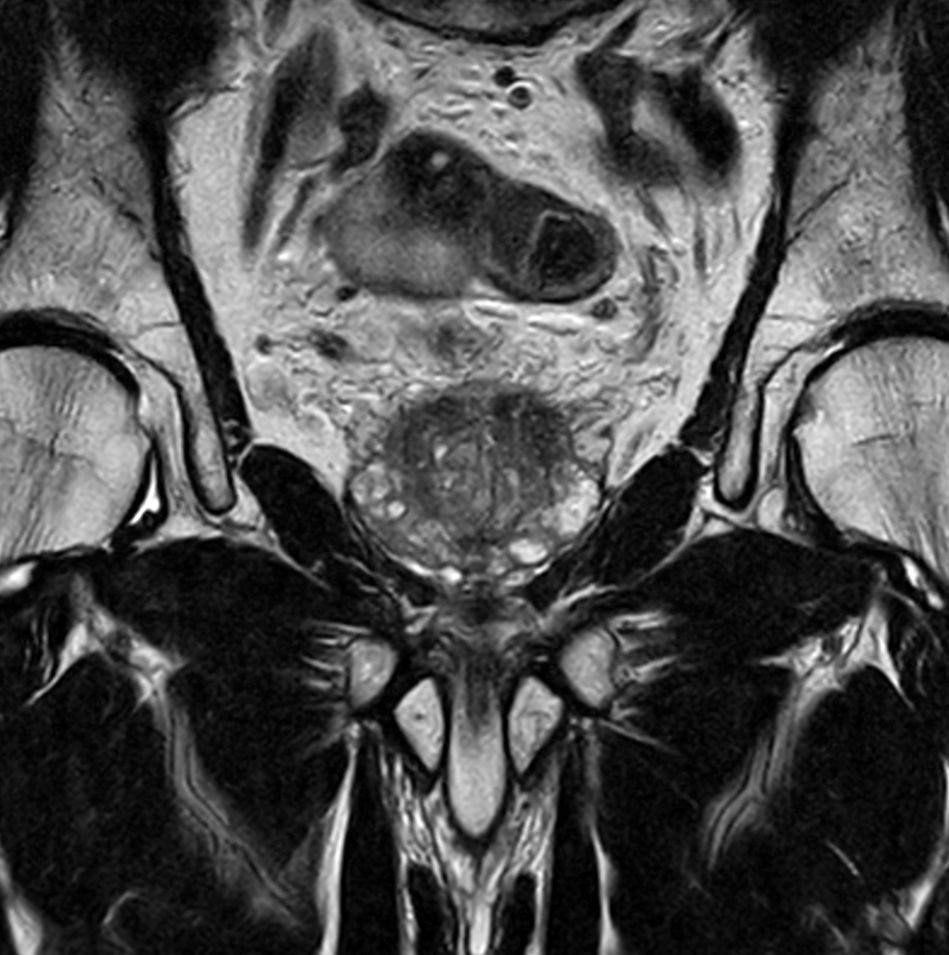

For prostate exams, the MSK M coil can be used in combination with the posterior coil, delivering exceptional quality MR images and high patient satisfaction.

Premium signal-to-noise ratio is achieved via dStream, providing outstanding image resolution.